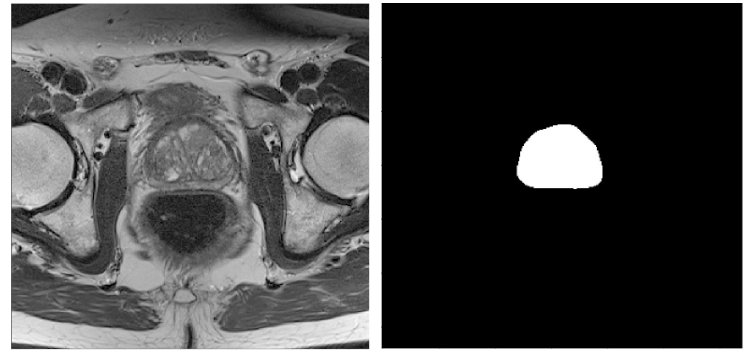

We provide scientific advisory and consultancy for various scientific tasks including planning of experiments, presentations of research, paper writing, hypothesis generation, statistical analysis, problem detection, problem solving and education in applied data science. In the images below you will find examples of the outcome of previous projects.

Segmentation of the prostate in 3D MRI